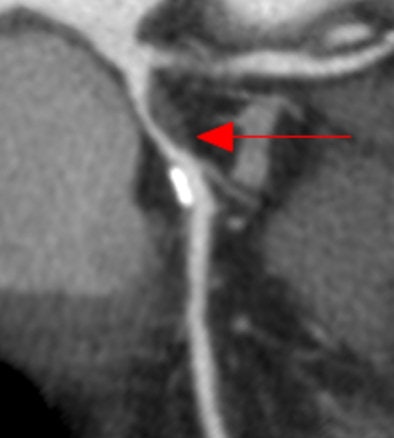

| Coronary CT angiography displayed as curved multiplanar reformation shows significant stenosis in the proximal left anterior descending coronary artery caused by noncalcified plaque. The lesion was correctly identified by the algorithm, and a true-positive detection mark (red arrow) was deployed. |

Quantitative catheter angiography detected 38 stenoses with ≥ 50% obstruction, of which the algorithm identified 28 (74%).

The CAD algorithm correctly identified 19/19 patients with 205 significant stenoses in any vessel and correctly excluded 206 significant stenoses in 26/40 patients.

"Particularly, the high NPV, in the range of 91-97% per vessel and 100% per patient, appear promising," Schoepf et al wrote. "Similarly, the comparatively low rate of false-positive detection marks sets this algorithm apart from computer-aided detection applications in other organ systems, which have traditionally struggled to find the right balance between high sensitivity and low false-positive rates. Furthermore, we found relatively high performance for diagnosing significant coronary artery stenosis on a per-patient level. However, per-vessel sensitivities showed considerable variation, with lower values than typically observed with human interpretation."